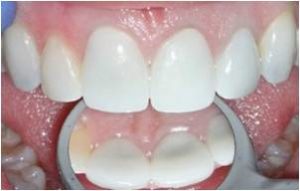

Digital Photography

Dr. Raymond will take high resolution digital photographs through the microscope during your consultation and treatment to help explain his findings, document his work, and communicate with your general dentist. These photographs allow you to better understand your dental needs and create a dialogue. Dr. Raymond believes that your needs and your understanding of those needs are the foundation of a beneficial doctor-patient relationship. The high resolution photographs are also shared with your general dentist allowing for more accurate communication, increased efficiency, and a better outcome for you.